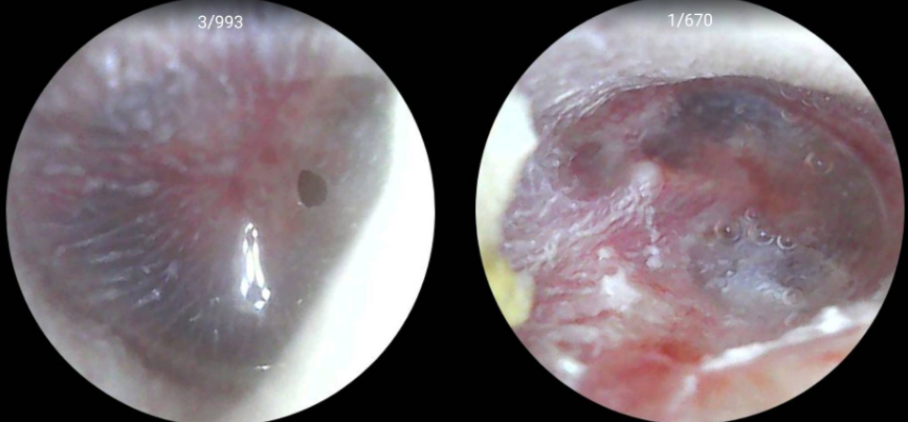

State-of-the-Art Digital Otoscope With our advanced digital otoscope, we offer high-resolution visuals of your ear canal and eardrum, aiding in the accurate assessment of various ear conditions. Our doctors will guide you through the examination process, explaining the findings in real-time. This approach not only educates but also involves you directly in your care, ensuring a transparent and informative experience. You'll have a better understanding of your ear condition and the proposed treatment plan.